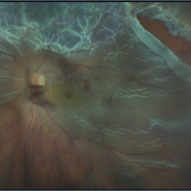

Total Rhegmatogenous retinal detachment with lattice degeneration & Vitreous haemorrhage

Jul 31 2023 by Harsh Vardhan Singh, MS

72-year male presented PVD induced total retinal detachment with vitreous hemorrhage

Photographer: Dr Harsh Vardhan Singh, AIIMS, Guwahati

Imaging device: Zeiss Clarus 700

Condition/keywords: chronic retinal detachment, hemorrhage, rrd